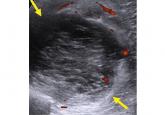

ArticleMusculoskeletal ultrasonography basicsAuthor:Patricia B. Delzell, MDPublish date: April 2, 2018Ultrasonography is emerging as a core method to evaluate musculoskeletal problems.Read More